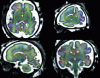

Magnetic Resonance Imaging (MRI) is frequently used for visualising the human brain, both for clinical and research purposes. However, due to their spectral and semantic complexity, MRI images of the brain are difficult to analyse. The human expert then need computer-based assistance. This article describes the main solutions that have been proposed for processing, analysing and modeling the anatomical information carried by brain MRI images. It also focuses on new advances related to recent modalities.

However, users of MRI images face a number of challenges related to the nature and content of these images. The first difficulty stems from the constant progress made by MRI scanner manufacturers. Two-dimensional images have now given way to 3D and even 4D images (images in space and time). Volumes of information are now so great that analysis by the human eye alone is no longer possible. Image resolution is also increasing, now reaching sub-millimetre values. This finesse of detail, combined with the very high anatomical complexity of the human brain, leads to a second difficulty, linked to the semantic analysis of MRI images, which – if based on human expertise – can no longer do without computer assistance.